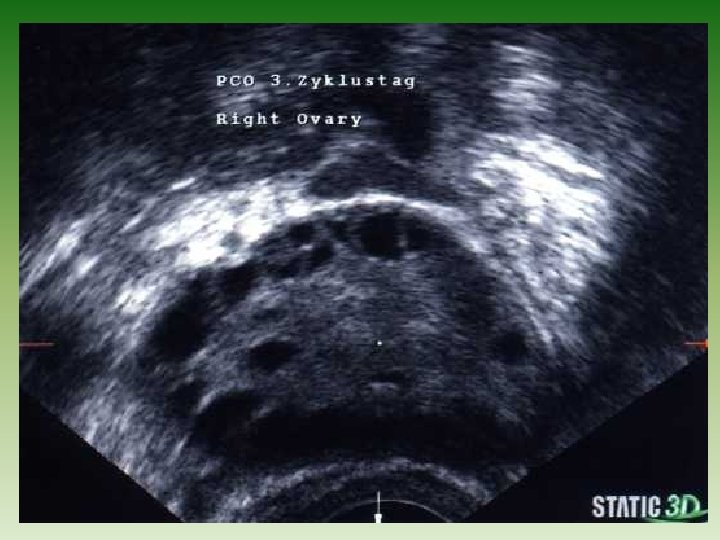

Grundsatzfrage: ist ein poycystisches Ovar tatsächlich ein PCO ? ? Tews, Wels, März 2017

Grundsatzantwort: die Bezeichnung PCO ist falsch, grundsätzlich handelt es sich um eine vermehrte Anzahl antraler Follikel die Bezeichnung: PFO – Syndrom wäre treffender Tews, Wels, März 2017

Grundsatzproblem man kann ein PCO – Syndrom haben, ohne PCO Ovarien zu besitzen. Tews, Wels, März 2017